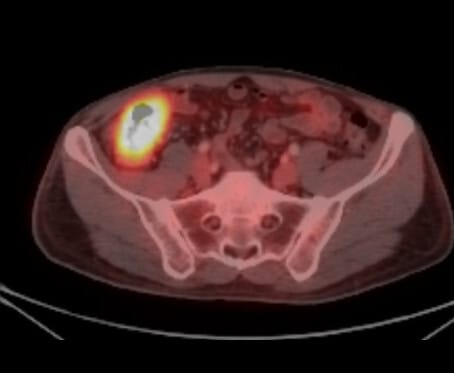

PET-CT 소견

🔵 Hot spot

암 부위가 FDG를 강하게 섭취하며 밝게 빛나는 병소로 나타납니다.

🔵 원격 전이 평가

간, 폐, 림프절 등 전이 병소의 고대사 영역을 확인할 수 있습니다.

Ibrahim D, Cecal cancer (PET-CT). Case study, Radiopaedia.org (Accessed on 15 Jul 2025) https://doi.org/10.53347/rID-91093